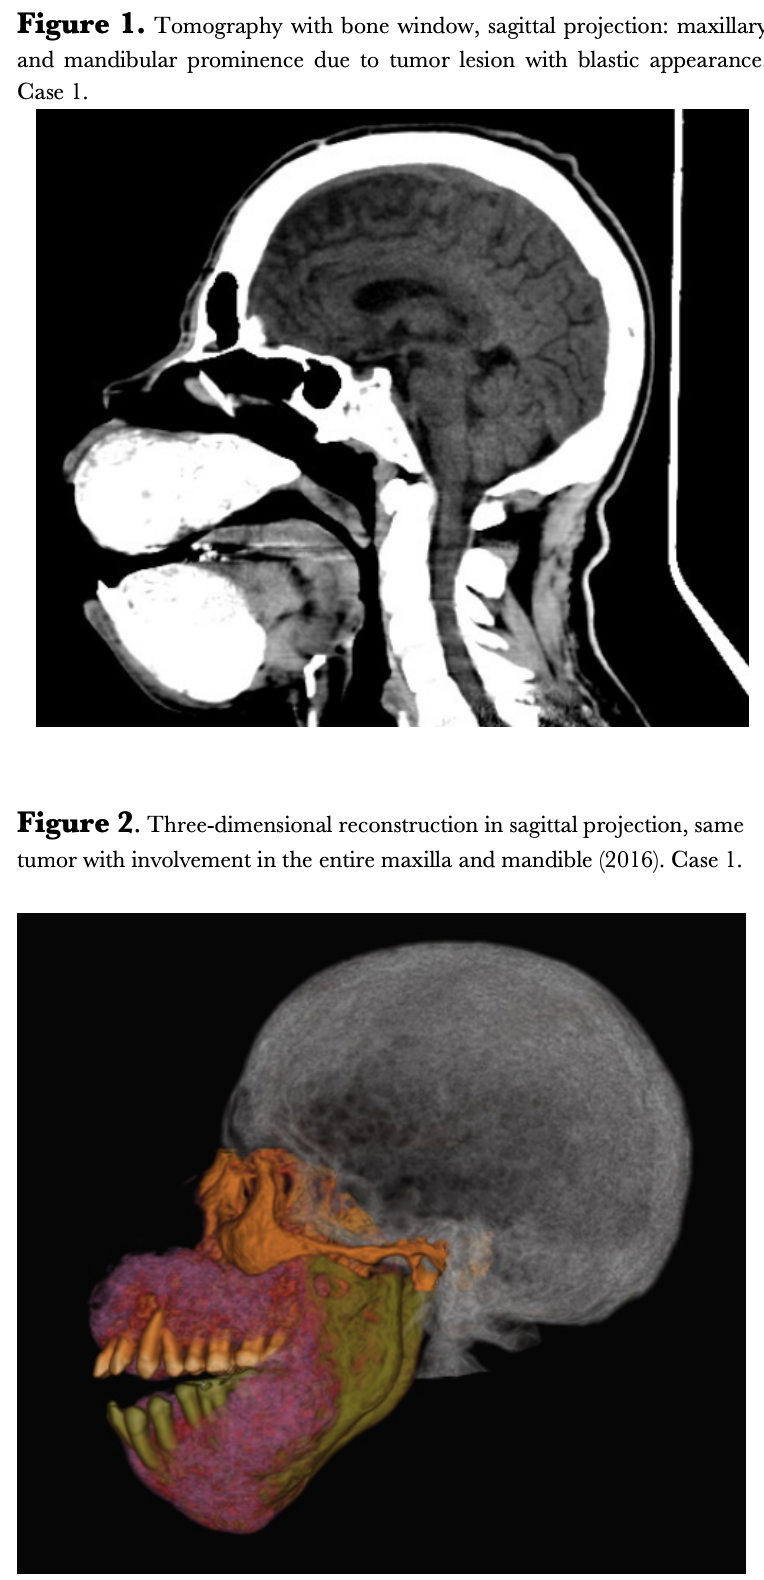

Cases: 8 cases are presented with ages between 17 and 35 years, serum parathyroid hormone levels between 1583 and 4715 pg/ml, and alkaline phosphatase levels between 146 and 2065 IU/L. All cases with brown tumors in the maxilla and mandible characteristic of Sagliker syndrome.